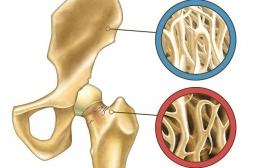

Densitométrie osseuse